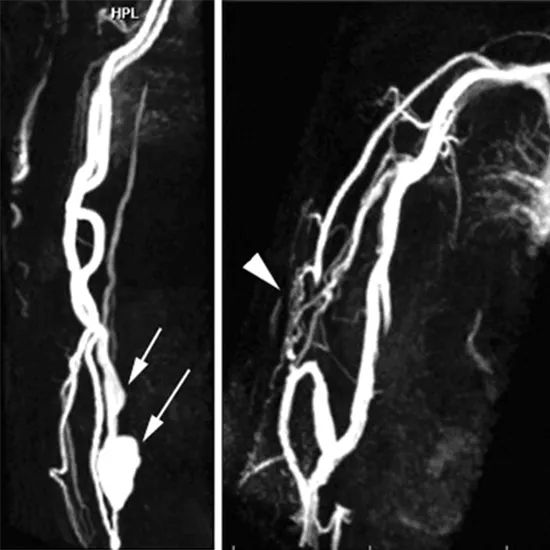

MR Angiography of the left upper limb is a non-invasive imaging methodology to diagnose left upper limb vascular pathologies. It provides a high-quality image of vessels in the left upper limb (arm, hand, and wrist). This procedure involves the use of contrast media for better views of the vessels. It helps doctors in establishing the correct diagnosis of the problem.

Doctors ask for a procedure of MR Angiography left upper limb to diagnose a broad range of vascular problems such as distal disease, hypothenar hammer syndrome, etc.